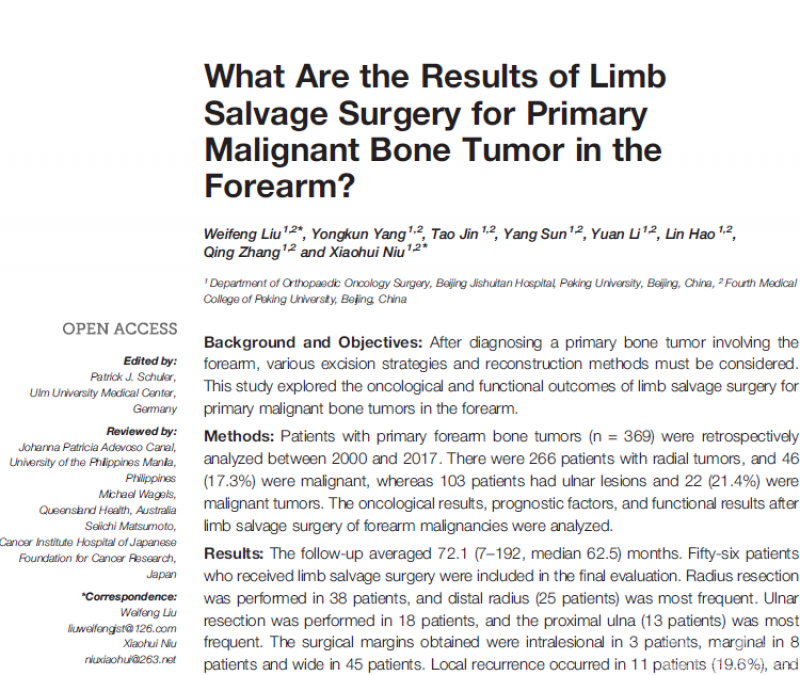

前臂原发恶性骨肿瘤发病率极低,前臂肌群解剖结构复杂且与手的精细运动密切相关,神经血管密布空间狭小。恶性骨肿瘤侵犯周围软组织往往造成重要神经血管受累而保肢困难。对于此部位的保肢手术缺乏足够的治疗和预后证据,而青壮年的上肢截肢势必给个人带来严重残障和家庭负担。

北京积水潭医院骨肿瘤团队,依靠优势的病例资源和长期随访证据,总结了近20年的前臂原发恶性骨肿瘤外科手术切除重建方法,统计分析出预后相关危险因素。为术前评估肿瘤切除安全边界、重建方式优劣提供了科学依据。该研究作为截止目前最大宗的前臂原发恶性骨肿瘤数据,为保肢治疗提供了安全切除评估要点、重建术式选择策略。为此类罕见肿瘤患者治疗提供了重要参考。